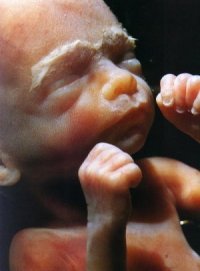

Semana 8:

O embrião tem agora cerca de 25 mm de comprimento. Traços faciais,

membros, mãos, pés, dedos e unhas tornam-se aparentes. O sistema

nervoso está receptivo e muitos dos órgãos internos começam

a funcionar.